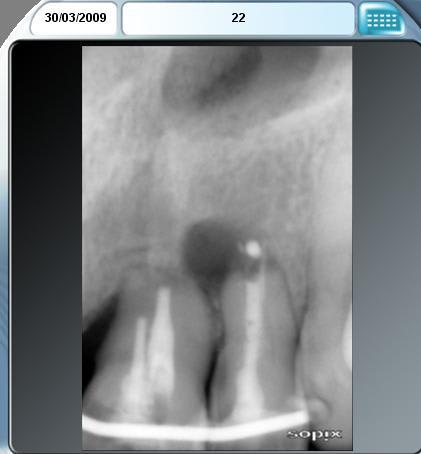

Scanner de contrôle quelques mois plus tard...

Preservation de crete - Eugenol

la procédure a permis de conserver le volume osseux disponible voir même l'augmenter, la difficulté est que le produit de comblement est radio-opaque et que sa cohésion est délicate à aprécier. peut -tu faire part de tes sensations lors du forage.